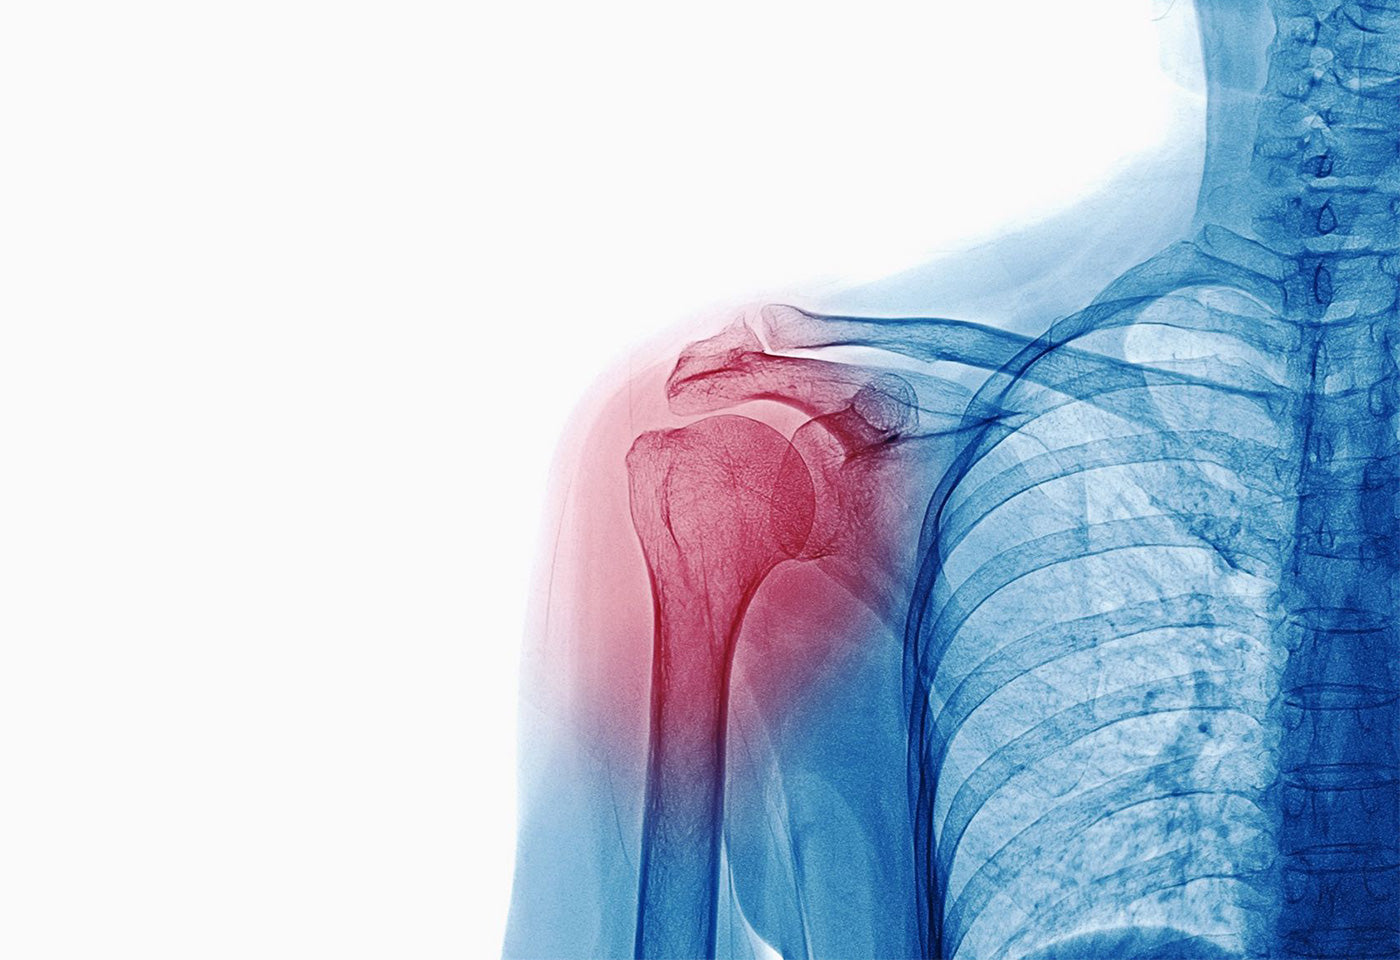

Because the shoulder is very mobile, it is highly vulnerable to secondary complications following a stroke or other neurological injuries. Shoulder subluxation, also referred to as inferior subluxation, is often seen in clients suffering from weakness in the arm due to hemiparesis. Typically, over time, this continued weakness causes the humeral head (ball of the humerus) to shift out of the socket (glenoid cavity) in a slightly downward direction. This is partly due to gravity pulling the weight of the humerus downward, and more importantly, also due to the lack of shoulder muscle strength resulting in the inferior displacement. The subluxation is palpable by feeling the space or gap between the top of the shoulder bone (acromion) and the top of the humerus (ball).